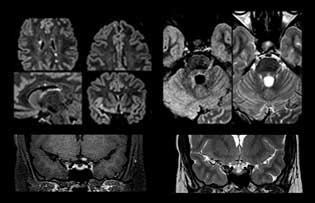

Dr. Savatovsky nutzt fünf oder sechs verschiedene ExamCards für die Bildgebung einer Raumforderung oder eines bekannten Tumors im Gehirn. „Wenn eine Raumforderung im Gehirn vorliegt, versuchen wir diese zu charakterisieren, um dem Neurologen die Informationen zur Festlegung des nächsten Schrittes zu liefern bzw. den Neurochirurgen bei der Vorbereitung eines Eingriffs oder einer Biopsie zu unterstützen. Für die Untersuchung nach einer Behandlung verfügen wir je nach Therapieform über verschiedene Protokolle und wir verfolgen spezifische Ansätze bei intra- und extraaxialen Tumoren.“ „Dies ist die umfassendste Untersuchung, die wir durchführen. Ingenia liefert aufgrund der guten räumlichen Auflösung und des hohen Signal-Rausch-Verhältnisses alle diese Daten. Außerdem ist das System so flexibel, dass damit kürzere Sequenzen möglich sind. Somit sind wir in der Lage, eine sehr umfangreiche Untersuchung in begrenzter Zeit vorzunehmen.“

„Die größte Herausforderung besteht in der sachgemäßen Charakterisierung der Läsion und der angemessenen Information des Chirurgen, zum Beispiel was die Position der Gefäße und der funktionellen Bereiche betrifft. Gelegentlich ist eine sehr umfassende Untersuchung notwendig, beispielsweise wenn eine Raumforderung an einem anderen Krankenhaus festgestellt wurde und der Patient anschließend an uns überwiesen wurde. Wir führen dann eine Charakterisierung der Läsion und eine präoperative Bildgebung in einer Untersuchung durch, d.h. sowohl eine morphologische als auch eine funktionelle Beurteilung. Für die morphologische Beurteilung verwenden wir eine T1-gewichtete Prä- und Postkontrastbildgebung sowie FLAIR für die Beurteilung der Infiltration und Diffusion. Für die funktionelle Charakterisierung führen wir eine Perfusionsbildgebung, eine MR-Spektroskopie und eine suszeptibilitätsgewichtete Bildgebung durch, um Mikrogefäße oder Mikroblutungen innerhalb der Läsion aufzuspüren[4]. Für die präoperative Untersuchung führen wir eine spezifische morphologische Bildgebung durch, die mit dem Navigationssystem kompatibel ist. Je nach Position des Tumors erfolgt fMRT oder TDI.“